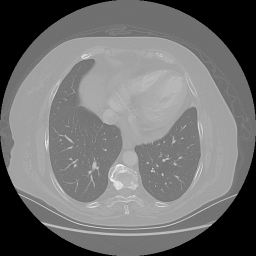

Reconstructed NATIVE CT scan (cycle consistency)

No window - Raw intensity values

Lung window (WL -600, WW 1500 β†’ Low βˆ’1350, High +150)

Mediastinum window (WL 40, WW 400 β†’ Low βˆ’160, High +240)